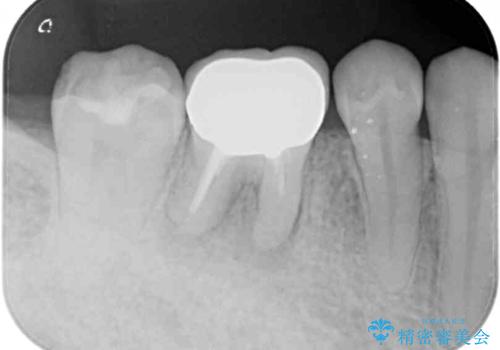

レントゲン写真より、根尖部に病変があったことから、根管治療を行い、症状消失後に補綴治療を行うこととしました。

補綴後6か月経過しレントゲンを撮影したところ、根尖周辺の病変が消失していることが確認できました。